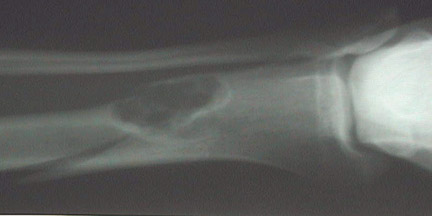

This radiograph demonstrates a

"pathologic fracture"

that has occurred as a consequence of weakening of the lower tibial metaphysis by a

lytic osteosarcoma

. The fracture extends to the lower left.